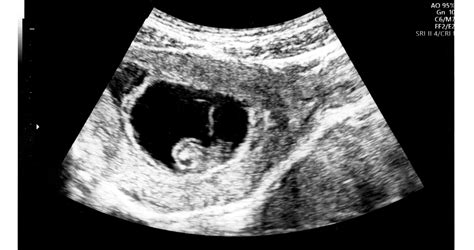

Az első ultrahangvizsgálat pillanata minden kismama emlékezetében élesen megmarad, amikor a monitor szemcsés szürkeségében először tűnik fel egy apró, dobogó pont, majd később a formálódó végtagok és az arc vonásai.

A HC (head circumference), vagyis a fejkörfogat mérése az egyik legstabilabb indikátora a magzati kornak és a fejlődés ütemének, különösen a második trimesztertől kezdődően. A fejkörfogat mérése azért bír kiemelt relevanciával, mert a magzat agyának növekedése közvetlen hatással van a koponyacsontok tágulására. Az emberi fejlődés során az agy az egyik leggyorsabban növekvő szerv, és ennek a burka, a koponya, hűen követi ezt a tágulást.

Az orvosi protokoll szerint a mérést egy speciális anatómiai síkban kell elvégezni, ahol látható a thalamus és a cavum septum pellucidum nevű agyi struktúra. Ez garantálja, hogy minden alkalommal ugyanabban a magasságban történjen a mérés, így az eredmények összehasonlíthatóak maradnak a hetek múlásával.

A várandósság során három kötelező nagy ultrahangvizsgálat van, és mindegyik más-más szempontból vizsgálja a fejkörfogatot. Az első trimeszteri szűrésen (12-13. hét) a HC még csak formálódik, ilyenkor inkább a fejtető-far távolság (CRL) a mérvadó, de az agyi struktúrák kezdeti alakulását már ekkor is figyelik. A valódi biometriai mérések a 18-22. hét között elvégzett genetikai ultrahangon kezdődnek.

A második trimeszterben a HC érték alapján ellenőrzik a magzati kor pontosságát. Ha a fogantatás időpontja bizonytalan volt, ilyenkor még pontosíthatják a szülés várható idejét. Ebben a szakaszban a legkisebb a variancia a magzatok között, az egyéni alkati különbségek inkább a harmadik trimeszterben kezdenek markánsan megmutatkozni.